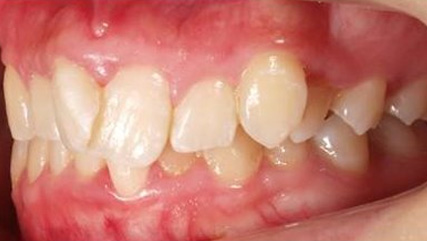

治療前

治療終了前